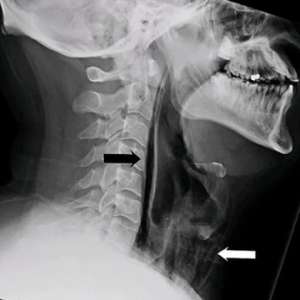

Мужчина испытал болезненные ощущения в области шеи, когда пытался сдержать чихание.

В результате чихания он ощутил «хлопок» в шее, после чего возникли проблемы с глотанием. МРТ-исследование показало, что воздух выходил через отверстие в трахее в мягкие ткани шеи. В течение нескольких дней мужчина получал питание через зонд, чтобы ткани могли зажить.

Когда мы сдерживаем чихание, воздух не может выйти наружу, и его давление разрывает мягкие ткани, причиняя им вред.